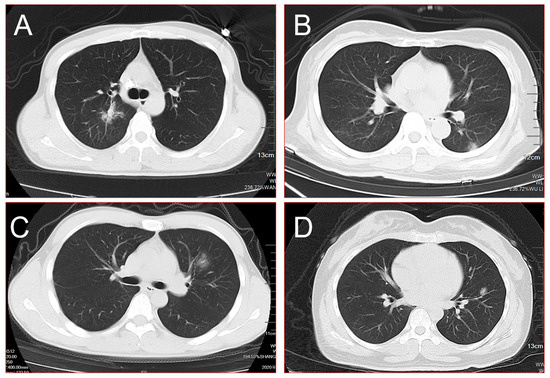

| Distribution | |

| Periphery distribution | 15 (71.4%) |

| Central distribution | 6 (28.6%) |

| Patterns of the SPN | |

| Burr sign | 16 (76.2%) |

| Lobulated sign | 13 (61.9%) |

| Pleural indentation | 9 (42.9%) |

| Smooth edges | 5 (23.8%) |

| Cavity | 3 (14.3%) |

| Density of the SPN | |

| Pure ground-glass nodule | 13 (61.9%) |

| Mixed ground-glass nodule | 8 (38.1%) |

| Diameter of the SPN | |

| <10 mm | 3 (14.3%) |

| 10 mm–20 mm | 8 (38.1%) |

| >20 mm | 10 (47.6%) |